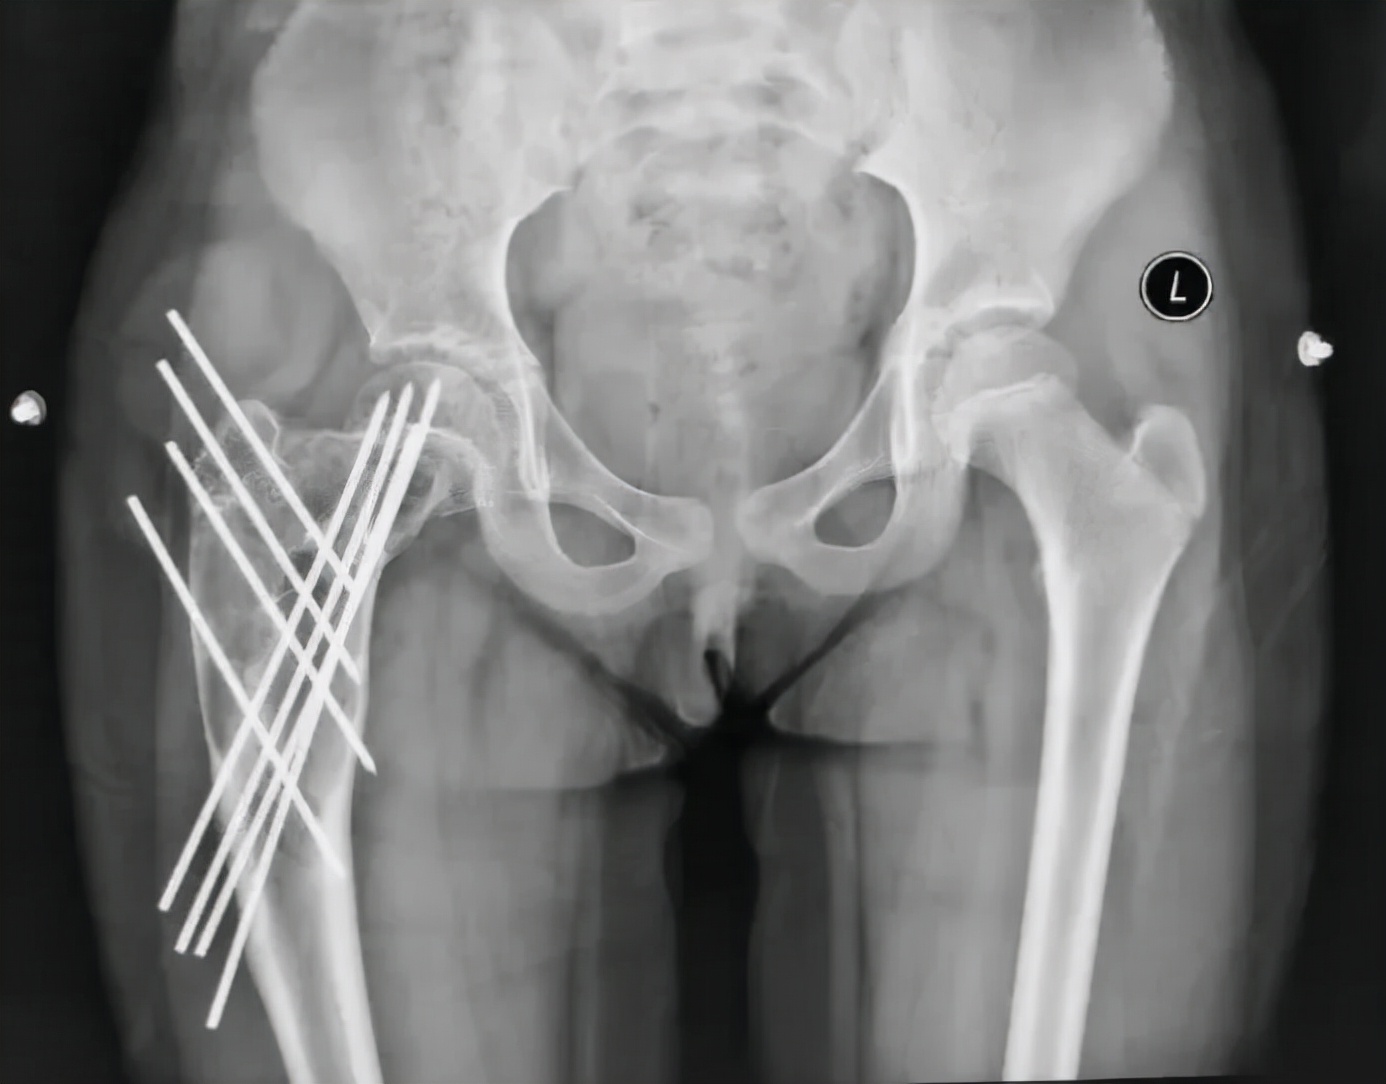

从影像学看,这个孩子手术后股骨近端留置多根钢针,术后2年左右的时间,尽管股骨强度有增加,但是骨囊肿还未愈合,并出现了部分退针的情况,孩子身高已经比第一次手术时长了近10cm了,选择什么样的治疗方案再次摆到面前,当我决定更换固定针,继续使用微创治疗理念时,患儿家长对于可能出现的针道激惹等并发症表示了完全的理解,并认真了解了术后相关的注意事项,正是因为家长的配合,手术之后患儿就能够进入快速康复。